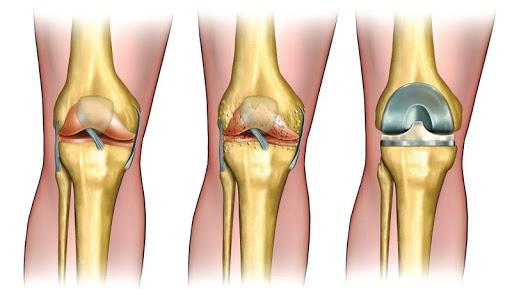

هل ترغب في التخلص من آلامك وأوجاعك نهائياً وتود معرفة سعر مفصل الفخذ السيراميكي ؟ آلام المفاصل واحدة من أكثر الآلام وجعاً والتي لا تذهب حتى من المسكنات، ويرجع السبب إلى تلف كامل وتآكل في تلك المنطقة لا يُجدي علاجها ولا يزول الألم، وتصعب معه ممارسة الأنشطة اليومية ومنها المشي، ليكون خيار إجراء الجراحة هو القرار الوحيد للتخلص من كل تلك الآلام. ولأن لكل مشكلة حل، ف الأطراف الصناعية واحدة من أبرز وأفضل الحلول في وقتنا الحالي التي أصبحت بديل آمن والحل الأفضل لتلك المشكلة التي يعاني منها كثير من الناس.

وتحدث تلك المشكلة نتيجة العديد من الأسباب منها التعرض إلى الحوادث، والتقدم في السن، وضعف المناعة والإصابة بالسمنة والمضاعفات التي تحدث نتيجتها من ضغط شديد على تلك المنطقة، وغيرها الكثير من الأسباب التي تسبب مشاكل كبيرة للجسم وخاصة الجزء السفلى، ومنها حدوث التهابات شديدة بمنطقة الورك التي تؤدي إلى الآلام شديدة بمنطقة الورك ويتطلب علاج تلك الحالة إجراء عمليات تغير المفصل واستبدال بآخر صناعي، وهى من الجراحات البسيطة والآمنة تماما، ويستطيع المريض بعدها أن يعيش حياته بشكل طبيعي، حيث يمكنه المشي والحركة بصورة طبيعية.

مفصل الركبة الأمريكى

يتساءل البعض كيف يتم تغير المفصل بمفصل آخر جديد وصناعي، توجد أنواع مفاصل يتم صناعتها من الدول المختلفة منها الألماني والأمريكي والصيني وغيرها من الأنواع التي تختلف جودتها من نوع لآخر وبالتالي السعر وهو ما يخبرك به الطبيب.

وتتم العملية بالقيام بتعقيم المريض وتجهيزه للعملية مع تخديره إما بمخدر موضعي مع منوم خفيف أو التخدير الكامل وهو أمر يحدده طبيب التخدير تبعاً لحالة المريض والوقت الذي ستستغرقه العملية.

تبدأ العملية من خلال قيام الجراح بعمل شقوق فوق الجزء الأمامي أو الجانبي من الورك من خلال طبقات الأنسجة، بعدها يتم إزالة العظام المريضة أو التالفة وكذلك الغضاريف مع ترك العظام السليمة دون المساس بها، ثم يقوم الطبيب بزراعة تجويف للأطراف الصناعية في عظام الحوض، لاستبدال التجويف التالف، وفي النهاية يتم استبدال الكرة المستديرة أعلى الفخذ بكرة صناعية والتي يجري تركيبها في الجذع المناسب في عظمة الفخذ.

يتم تعريف تلك العملية بأنها عملية جراحية يتم من خلالها استبدال مفصل الورك كاملاً بمفصل صناعي من المعدن أو البلاستيك، وتتم تلك العملية تحت تأثير التخدير النصفي لمنطقة الجراحة أو بالتخدير العام للجسم كله، إذ يكون المصاب عندها غائبًا عن الوعي، وتهدف إلى استبدال العظمتين التالفتين لخلق مُسطّحين جديدين في المفصل ليعمل المفصل أفضل، ويقوم الطبيب بتحديد طريقة التخدير المستخدمة بناءً على وضع المصاب، وحالته الصحية.